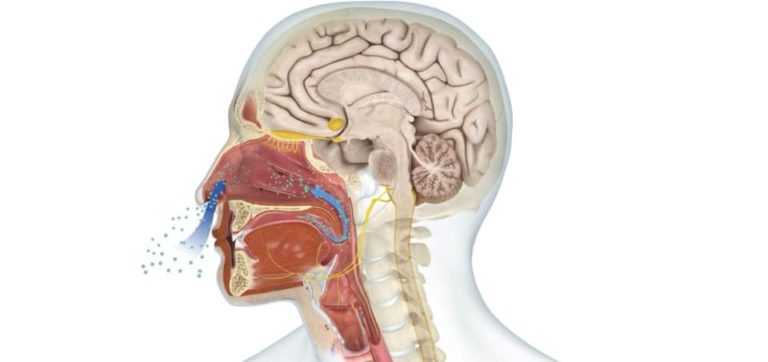

Our sense of smell is more powerful than we realize!